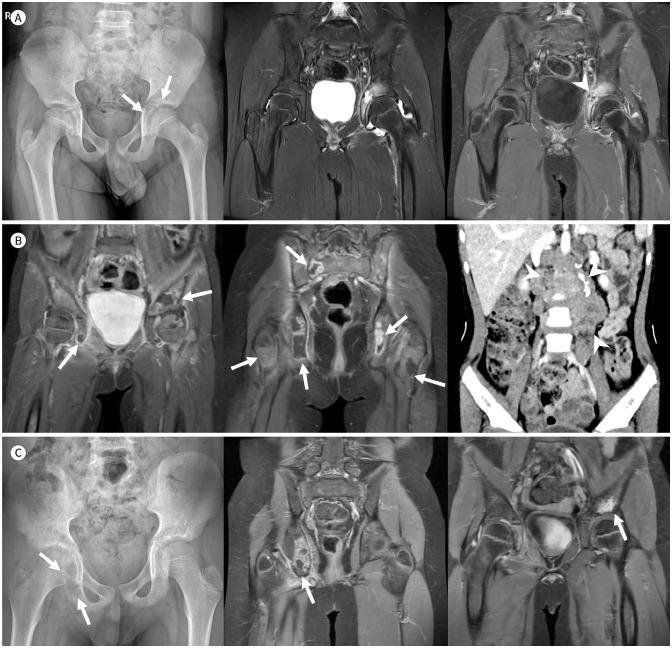

Developmental dysplasia of the hip is a condition characterized by hip joint instability due to acetabular dysplasia in infancy, necessitating precise ultrasound examination. Legg-Calvé-Perthes disease is caused by a temporary disruption in blood flow to the femoral head during childhood, progressing through avascular, fragmentation, re-ossification, and residual stages. Slipped capital femoral epiphysis is a condition where the femoral head shifts medially along the epiphyseal line during adolescence due to stress, such as weight-bearing. Differentiating between transient hip synovitis and septic arthritis may require joint fluid aspiration. Osteomyelitis can be associated with soft tissue edema and osteolysis. When multiple lesions are present, it is essential to distinguish between Langerhans cell histiocytosis and metastatic neuroblastoma. This review will introduce imaging techniques and typical findings for these conditions.

发育性髋关节发育不良是一种因婴儿期髋臼发育不良导致髋关节不稳定的病症,需要进行精确的超声检查。Legg-Calvé-Perthes病是由儿童期股骨头血液供应暂时中断引起的,历经缺血、碎裂、再骨化和残留阶段。股骨头骨骺滑脱是一种在青春期由于负重等压力导致股骨头沿骨骺线向内侧移位的病症。区分暂时性髋关节滑膜炎和化脓性关节炎可能需要进行关节液抽吸。骨髓炎可伴有软组织水肿和骨质溶解。当出现多个病灶时,区分朗格汉斯细胞组织细胞增多症和转移性神经母细胞瘤至关重要。本综述将介绍这些病症的影像学技术和典型表现。